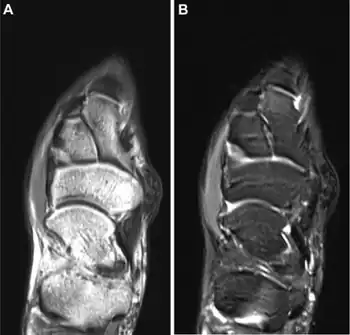

| a,b)MRI appearance of surfers' knot medial to the persons' navicular | |